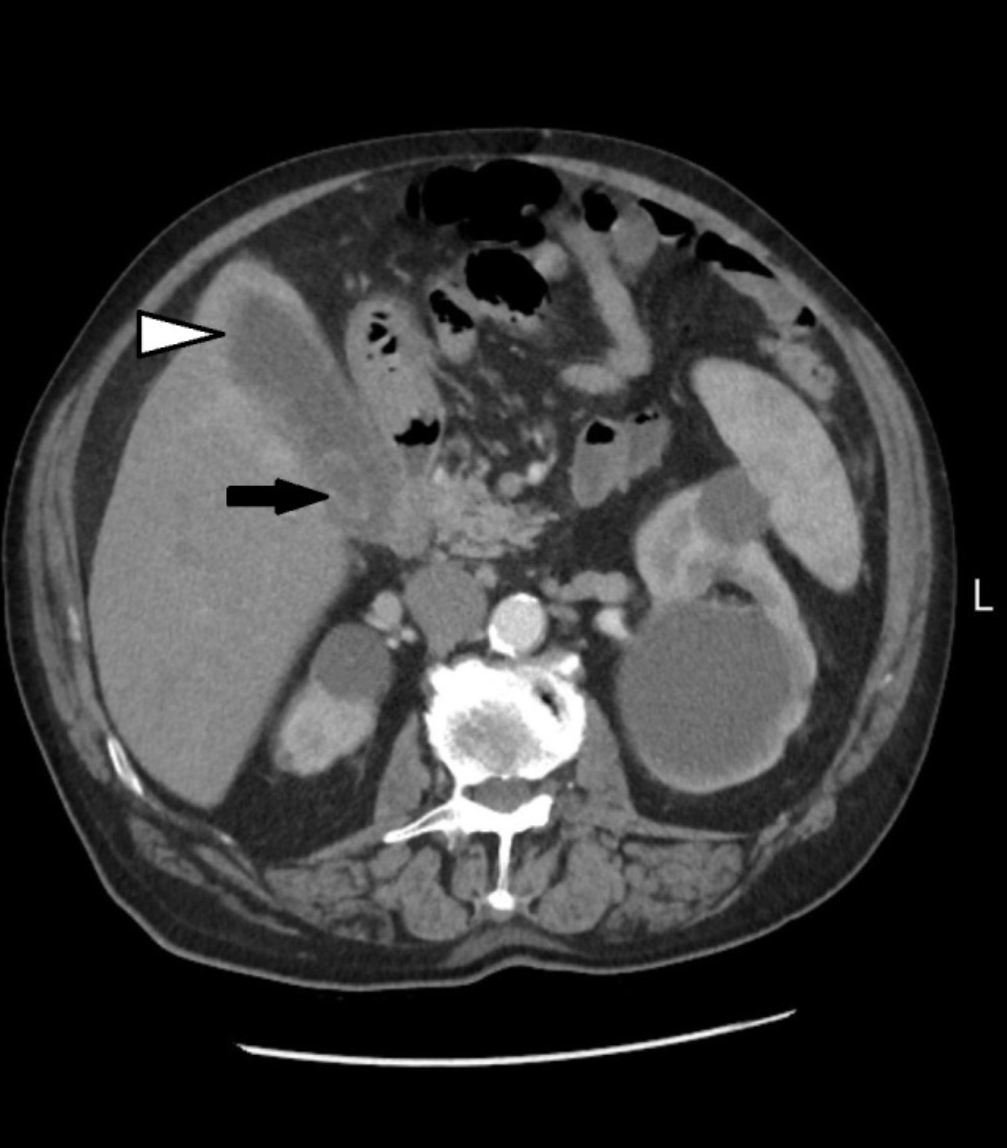

Abdominal multislice computed tomography (MSCT) subsequently confirmed acute gangrenous cholecystitis (Figure 2) and was used for preoperative assessment and surgical planning.

Figure 2. MSCT of the abdomen showed an enlarged gallbladder, thickened gallbladder wall (white arrowhead), and a calculus (black arrow)